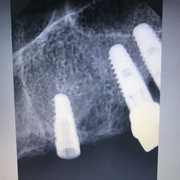

Дмитрий Л. Опубликовано 22 мая, 2019 Поделиться Опубликовано 22 мая, 2019 Коллеги, подскажите пожалуйста, чем биогоризонт запротезировать? 10 лет назад кто-то ставил. Трансфер от миса подошел, но как-то неидеально. Внутренний 6гранник, желтый, 3,5. Ссылка на комментарий

Дмитрий Л. Опубликовано 23 мая, 2019 Поделиться Опубликовано 23 мая, 2019 Я правильно определил, что это биогоризонт 3.5? Ссылка на комментарий

dentikl Опубликовано 23 мая, 2019 Поделиться Опубликовано 23 мая, 2019 3,8. у 3,5-фиолетовое 1 Ссылка на комментарий

Борис80 Опубликовано 12 июня, 2019 Поделиться Опубликовано 12 июня, 2019 (изменено) Я правильно определил, что это биогоризонт 3.5? всё верно, стандартная платформа от Израиля, который с биогора и срисован изначально Изменено 12 июня, 2019 пользователем Борис80 1 Ссылка на комментарий